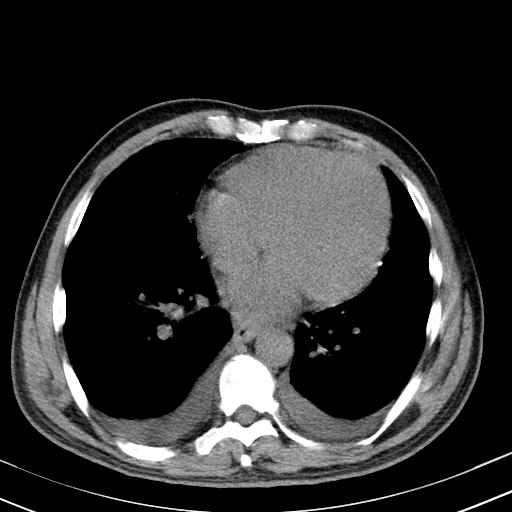

以下是引用zxl51642在2010-3-21 17:06:00的发言:[br]右下中心型肺癌并阻塞性肺炎/不张,纵膈淋巴结肿大,右侧大量胸腔积液,左侧少量胸腔积液,少量腹水。建议纤维支气管镜进一步检查。